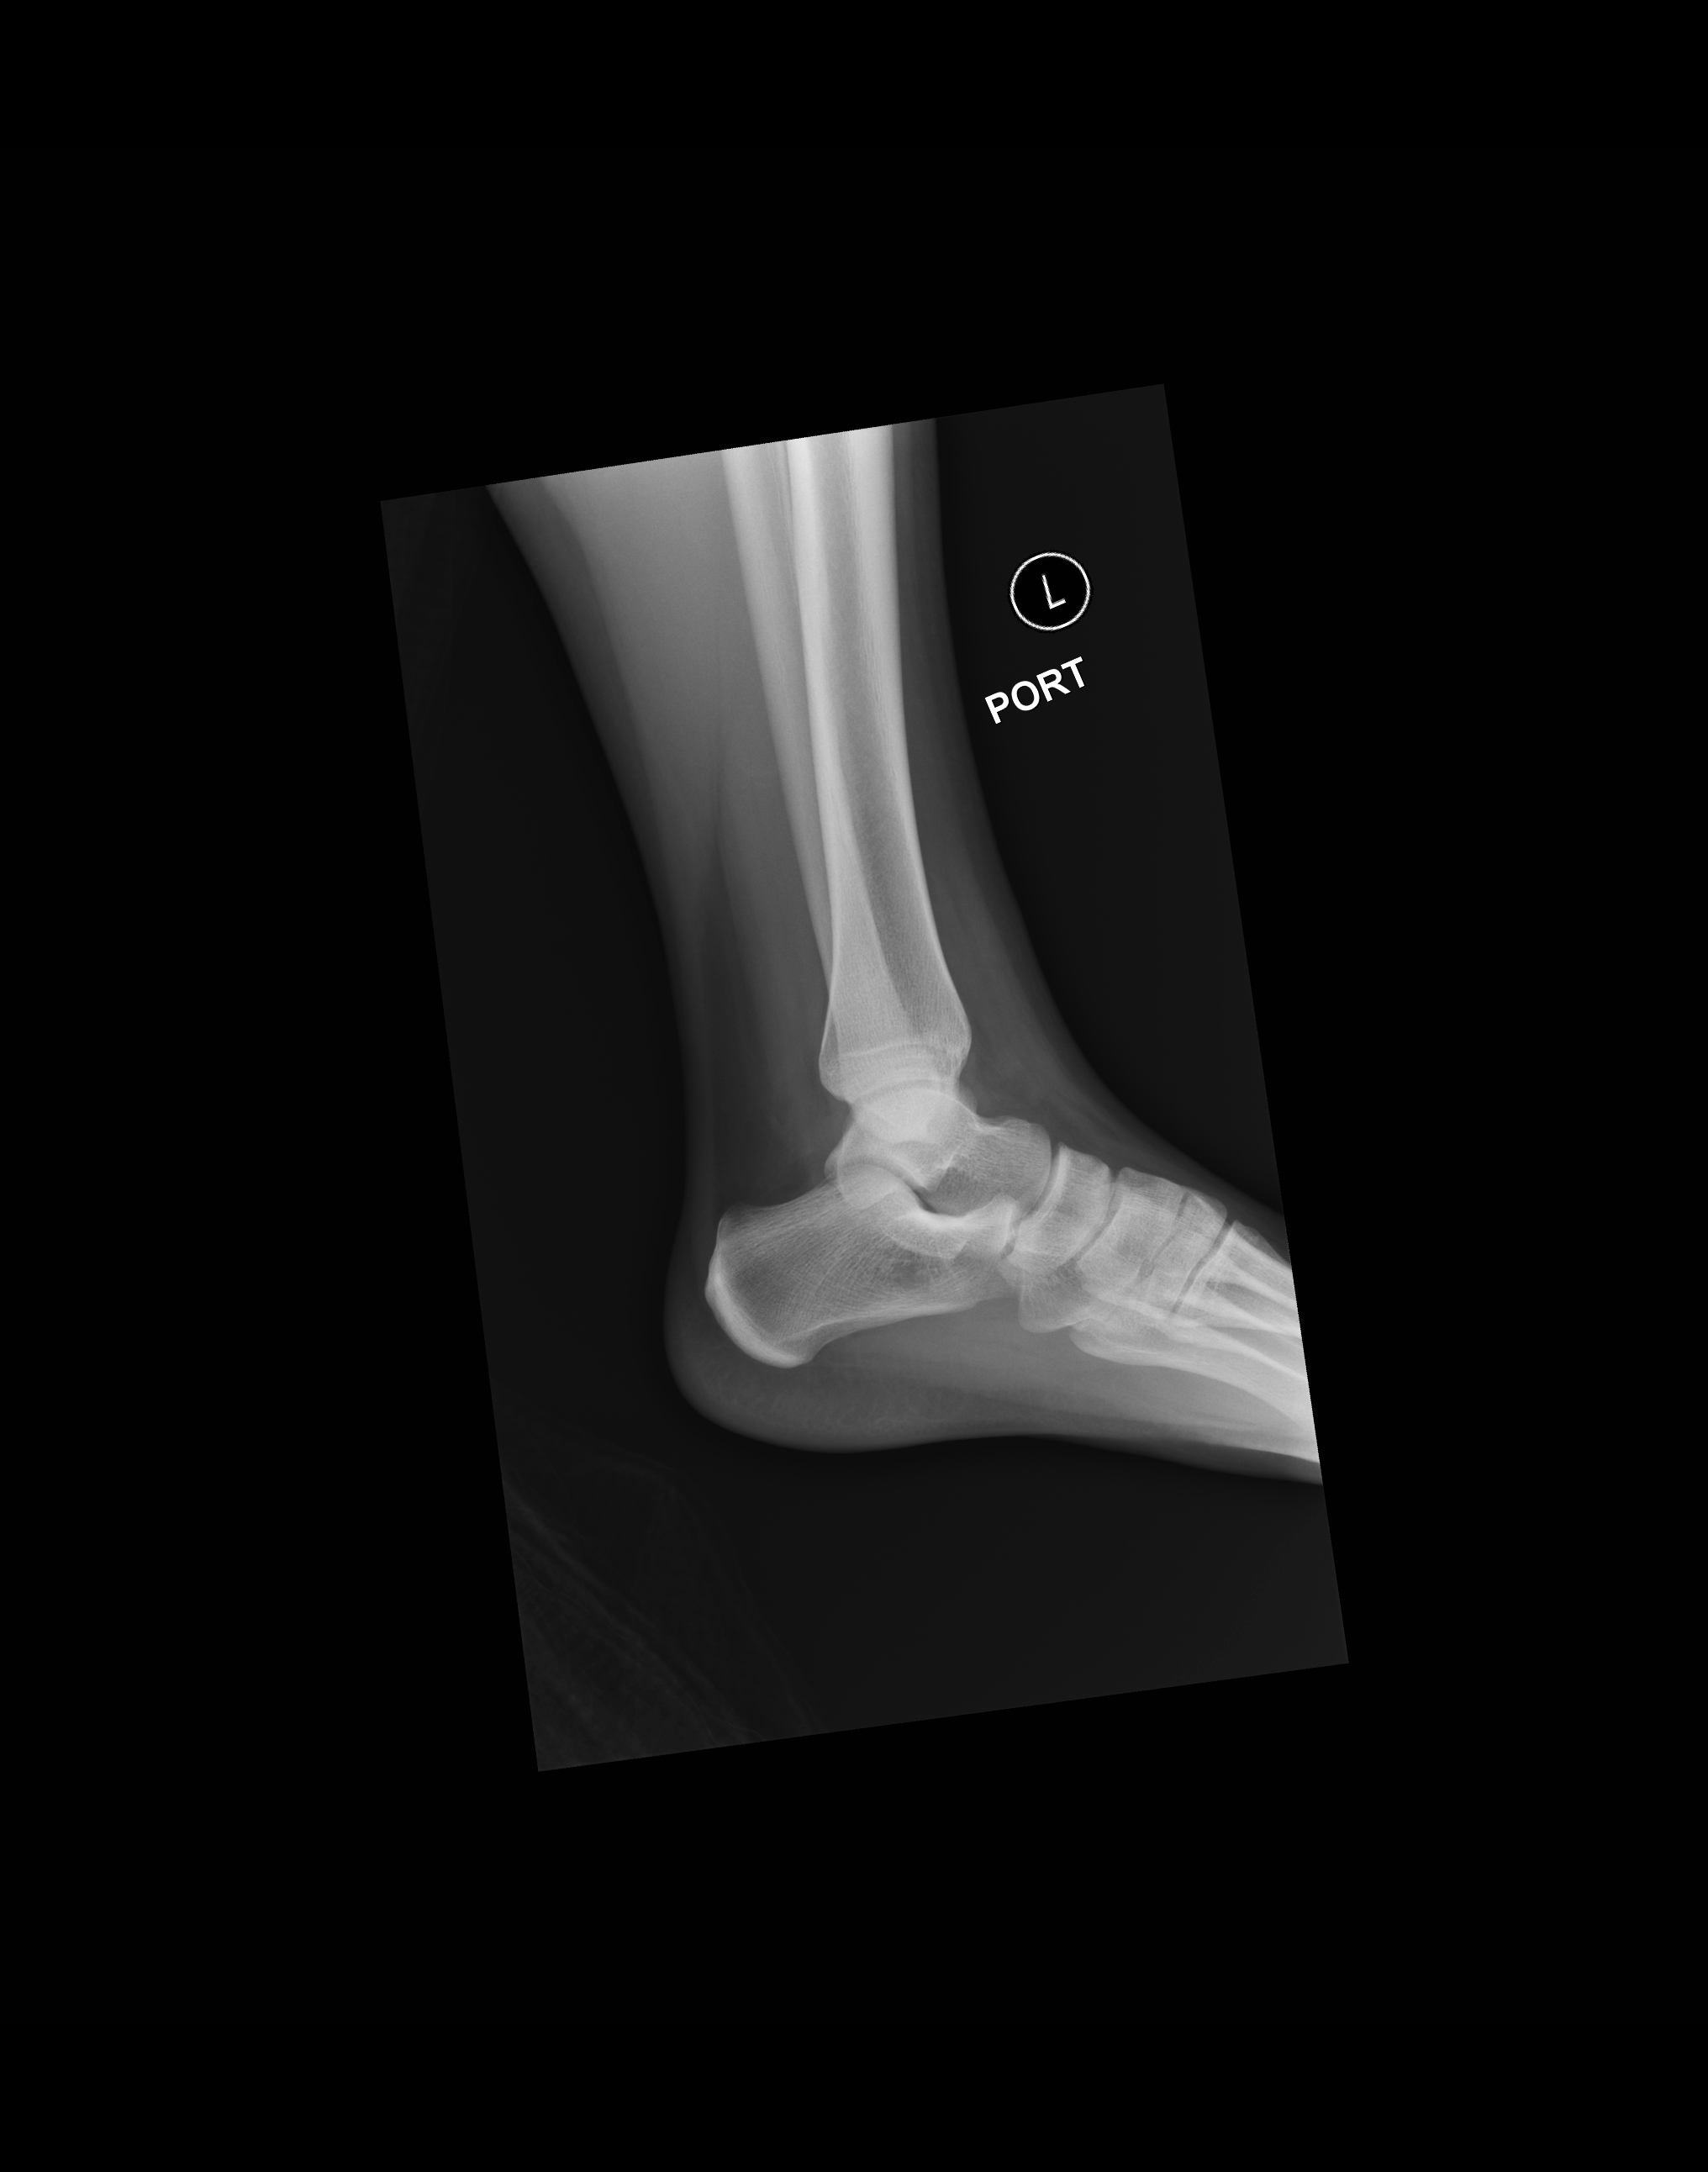

From geekymedics.com

Ankle Xray Interpretation Ankle Fracture Geeky Medics Calcaneus X Ray Angle This web page covers the epidemiology, anatomy, classification, presentation, imaging, and treatment of calcaneus fractures. The data provide a set of standard foot and ankle measures and nomenclature for preoperative planning and intraoperative and postoperative evaluations. A study of 24 healthy feet to quantify the normal foot and ankle angles, measures, and reference points from ap, lateral, and axial views.. Calcaneus X Ray Angle.